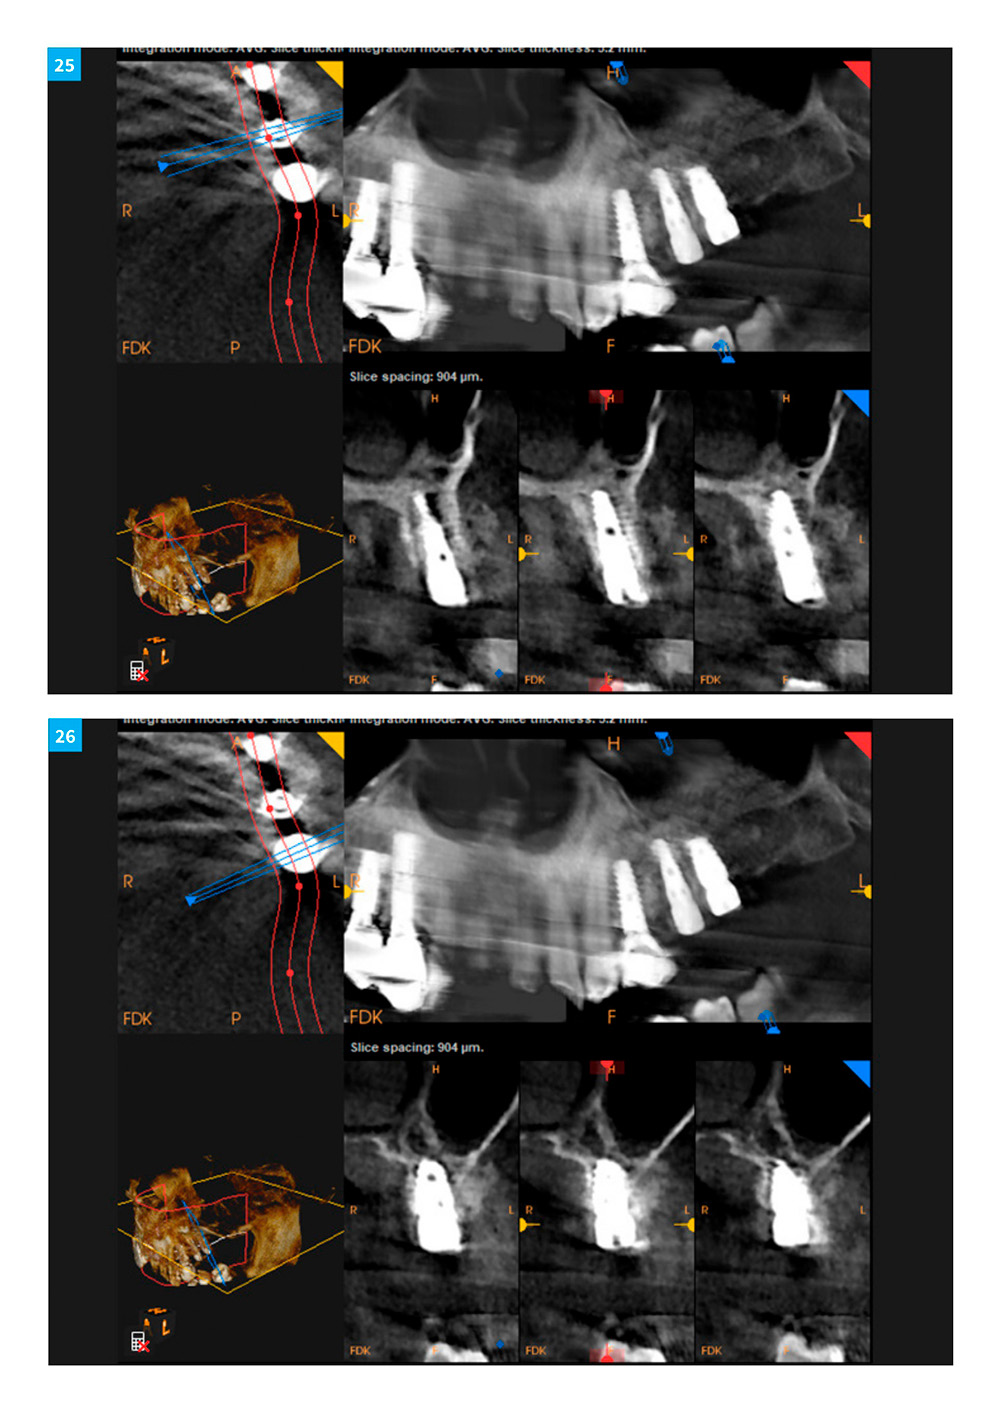

Dental Implant Continuum with DSI implants and products. Case 10

A year-long hands-on surgical program in Orange County & Silicon Valley, California. DSI Implants & products used exclusively.